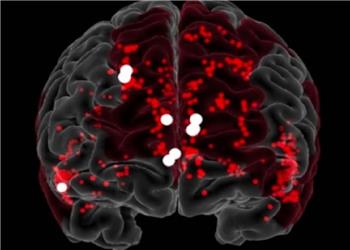

کرونا مغز همه را پیر کرد!

ایران پرسمان - خراسان / مطالعه جدیدی نشان داده که ویروس کرونا (COVID-۱۹) حتی اگر به آن مبتلا نشده باشید احتمالاً مغز تمام انسانها را پیر کرده است. محققان بریتانیایی ...